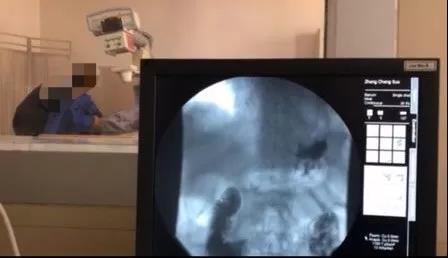

患者術(shù)后行上消化道造影檢查顯示:吻合口通暢,平臥位甚至頭低30°無(wú)明顯反流。

在過(guò)去的20年里,近端胃癌的發(fā)病率顯著升高。為了保留部分胃功能,減少營(yíng)養(yǎng)性并發(fā)癥,很多醫(yī)院采用近端胃切除。但與全胃切除相比,近端胃切除易出現(xiàn)反流性食管炎和吻合口狹窄等并發(fā)癥。目前,近端胃切除后消化道重建方式主要包括食管胃吻合(Esophagogastrostomy,EG )、間置空腸(jejunal interposition,JI)和雙通道重建(double tract reconstruction,DTR )。腹腔鏡下近端胃切除食管胃Kamikawa吻合技術(shù),與上述3種吻合方式比較,食管胃吻合口處肌瓣包裹重建,相當(dāng)于"再造賁門" ,減少反流性食管炎發(fā)生。同時(shí),利用胃前壁漿肌瓣覆蓋吻合口,降低了吻合口瘺?;颊咝g(shù)后恢復(fù)快、進(jìn)食早、吞咽通暢、無(wú)反流等不適,術(shù)后消化道造影提示“吻合口通暢,無(wú)明顯反流”。該術(shù)式具有很好的臨床應(yīng)用前景。